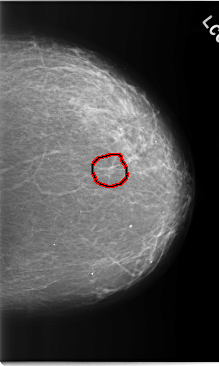

C_0205_1.LEFT_CC

LEFT_CC LINES 5856 PIXELS_PER_LINE 3496 BITS_PER_PIXEL 12 RESOLUTION 50 OVERLAY

FILE: C_0205_1.LEFT_CC.OVERLAY

TOTAL_ABNORMALITIES 1

ABNORMALITY 1

LESION_TYPE MASS SHAPE IRREGULAR MARGINS SPICULATED

ASSESSMENT 4

SUBTLETY 4

PATHOLOGY MALIGNANT

TOTAL_OUTLINES 1

BOUNDARY